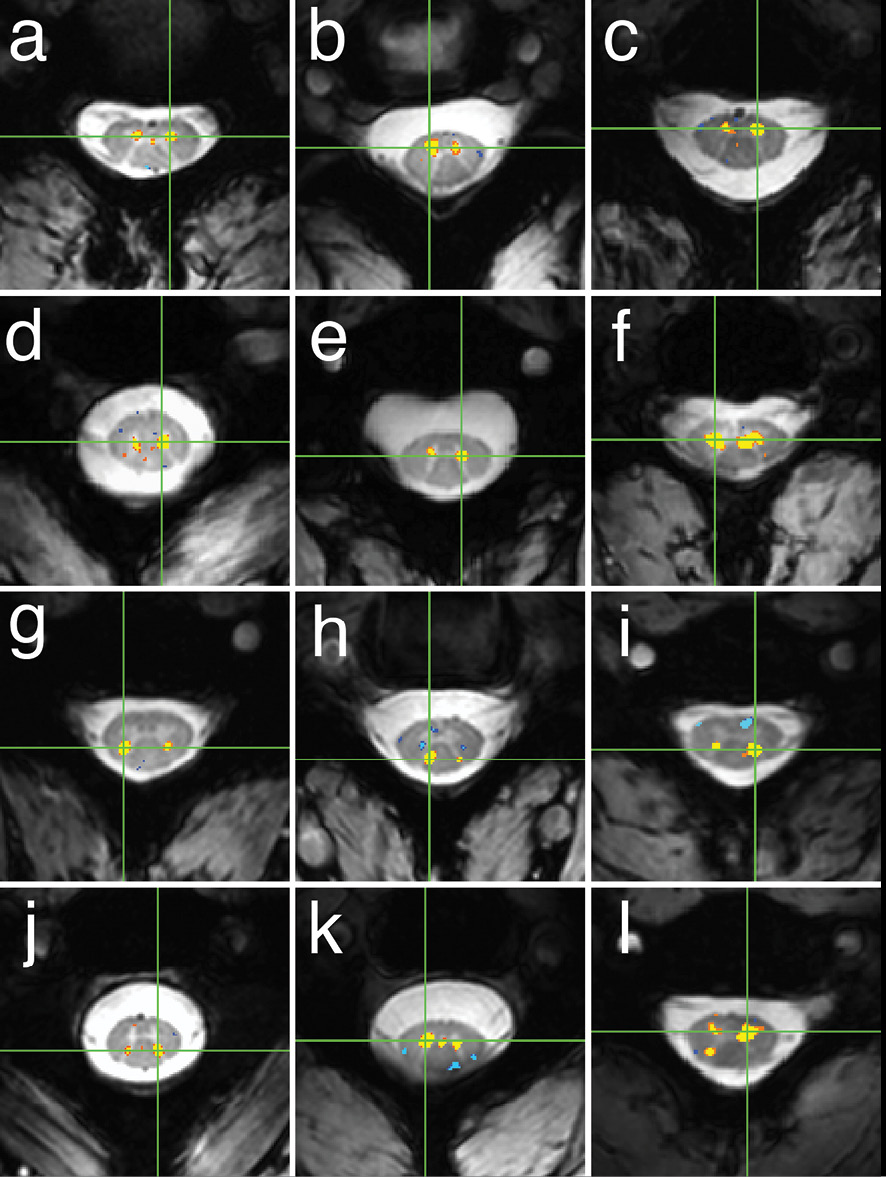

Examples of within-slice resting state functional connectivity across subjects

Examples of within-slice resting state functional connectivity across subjects. These analyses were performed using AFNI's ‘InstaCorr’ with p < 0.001 and no minimum cluster size. In each panel, a seed voxel is marked with a green crosshair and resultant correlations are overlaid on the anatomical image. (A–F) Connectivity between ventral horns for subjects 1, 3, 8, 10, 11 and 13 respectively. (G–J) Connectivity between dorsal horns for subjects 5, 16, 18 and 22, respectively. (K and L) Less common correlations within gray matter. In (K) (subject 20), focal connectivity between ventral horns and with central gray matter. In (L) (subject 7), connectivity between ventral horns but also with the contralateral dorsal horn. At the single-subject level, there is some evidence for functional connectivity between ventral and dorsal horns, but such correlations are less common across slices and not statistically significant at the group level. Images courtesy eLifesciences.